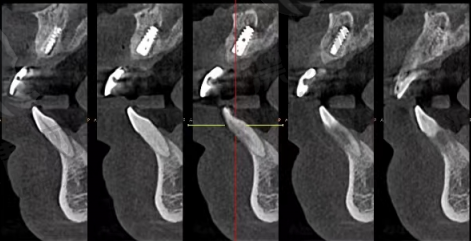

技术亮点:主打数字化种植,采用CBCT、种植导板,有效提升正确率。

技术亮点:引进瑞士士卓曼、韩国登腾等种植系统,重视术前CT定位。

技术亮点:3Shape扫描仪、德国sirona全景机,全程可视化种植流程。